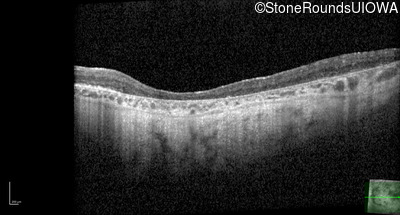

Optical Coherence Tomography - Right - 20/200 +2

Exemplar / OCT Stack